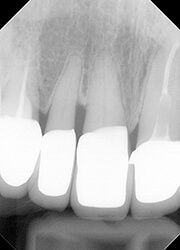

【治療後】

最終補綴物が装着されたところです。

植わっている歯根の長さは短くなりましたが、日常的には問題ありません。

歯髄も守られましたし、何より白黒がはっきりとした無病である状態に持って行くのが大切です。

抜髄、あわよくば抜歯になりそうなケースも、部分矯正を用いることで健全な状態に補綴することが出来ました。